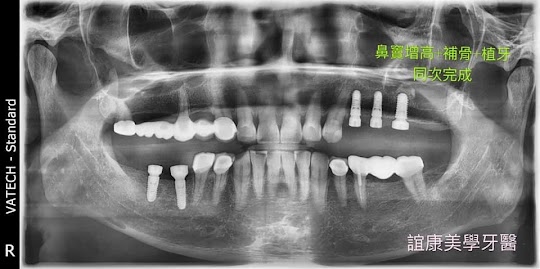

三個願望一次滿足(補骨+鼻竇增高+植牙)

透過3D斷層掃描知道患者鼻竇的高度,安全精準增加植體植入空間,並補入骨粉。